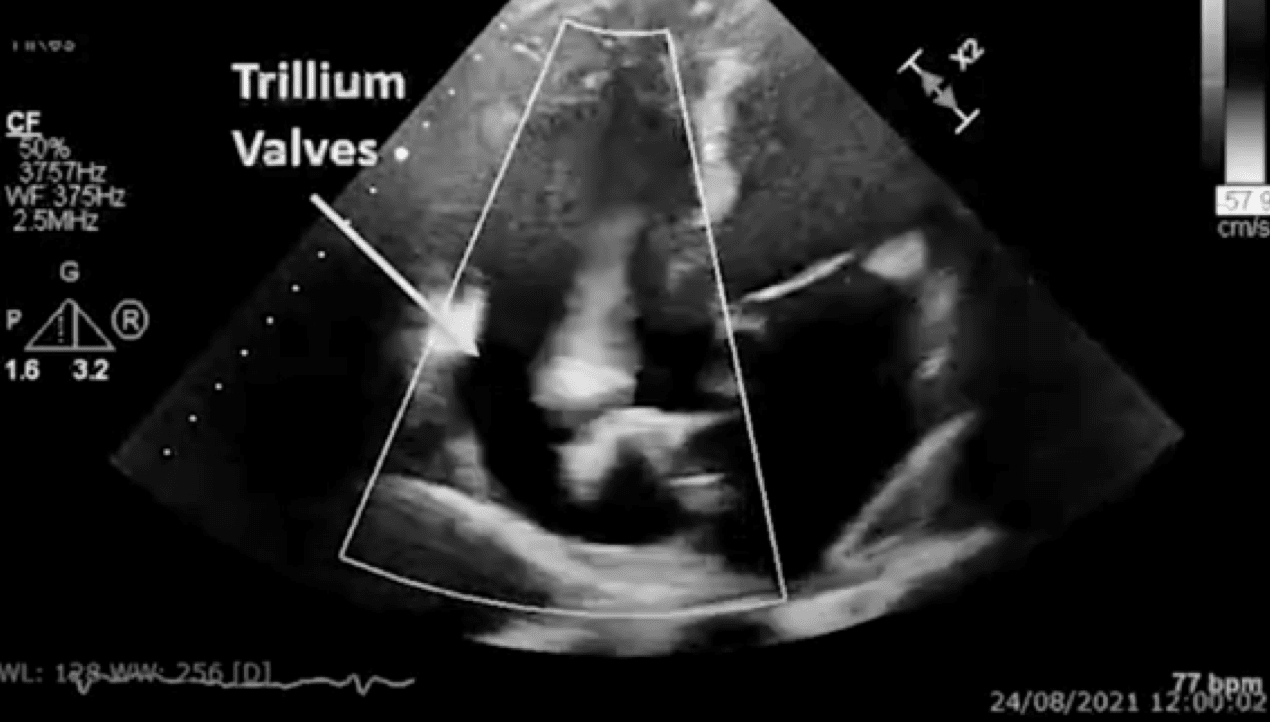

OngoingTrillium™ Early Feasibility Study (EFS)

in the treatment of severe or greater tricuspid regurgitation (TR).

Saving Lives While Gaining Clinical Expertise

Our clinical experience extends beyond clinical trials, with compassionate procedures demonstrating our ability to provide quality care even to patients currently deemed untreatable.

With many successful procedures in Belgium, Spain, Germany, Georgia, and Canada, we have improved patients’ lives while showcasing the capabilities of our entire portfolio: Trillium™, Koala™, and Unica™.